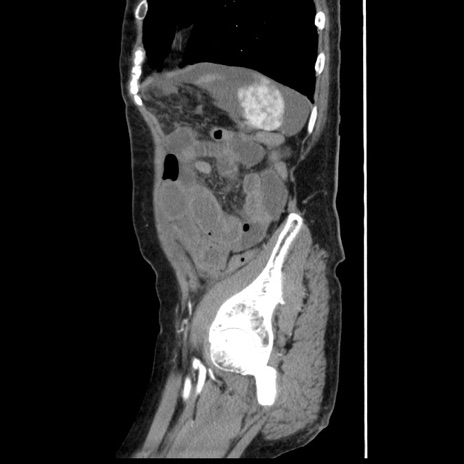

症例1(矢状断像)

【症例】80歳代女性

【主訴】腹痛

【現病歴】8時間前から腹痛あり来院。

【既往歴】糖尿病、脂質異常症、子宮体癌にて子宮全摘術

【身体所見】意識清明・会話良好だが腹痛で苦悶様、全腹部にわたって反跳痛と圧痛あり

【データ】WBC 13600、CRP 0.14、LDH 224、CK 90